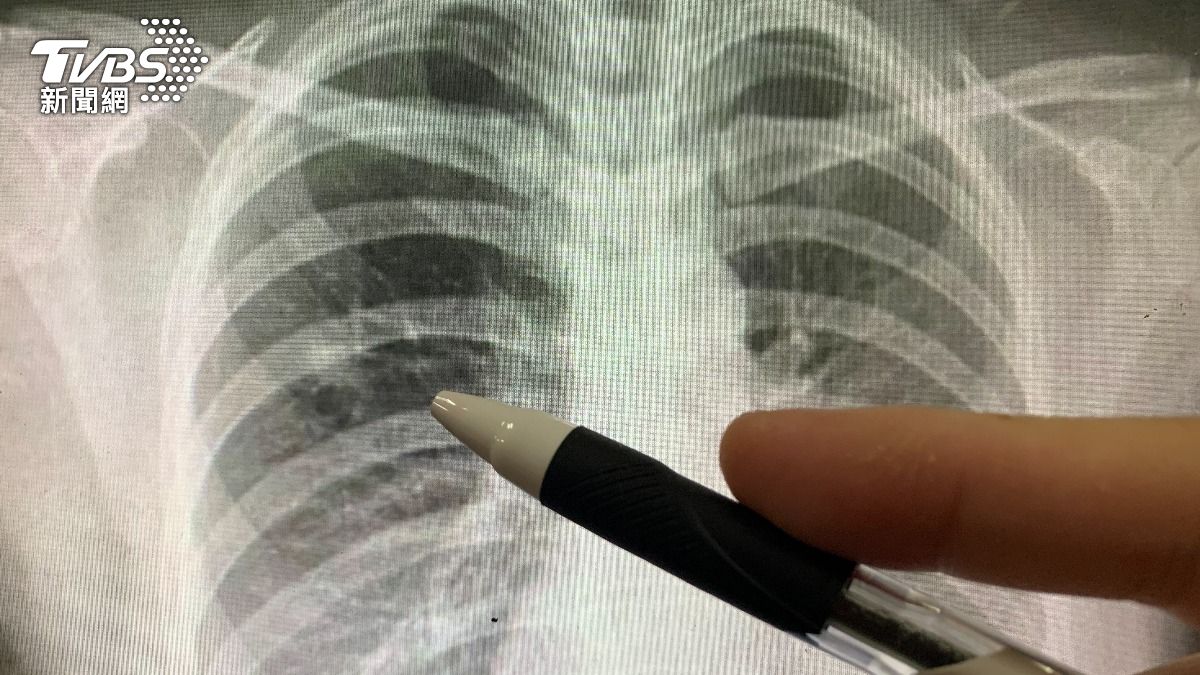

These include cancer, with lung cancer ranked first, followed by pneumonia (third), COVID-19 (sixth), and Chronic Obstructive Pulmonary Disease (COPD) (ninth).

Lung cancer topped three categories in Taiwan: it was the number one cause of death, the most common type of cancer, and the disease that cost the health insurance system the most.